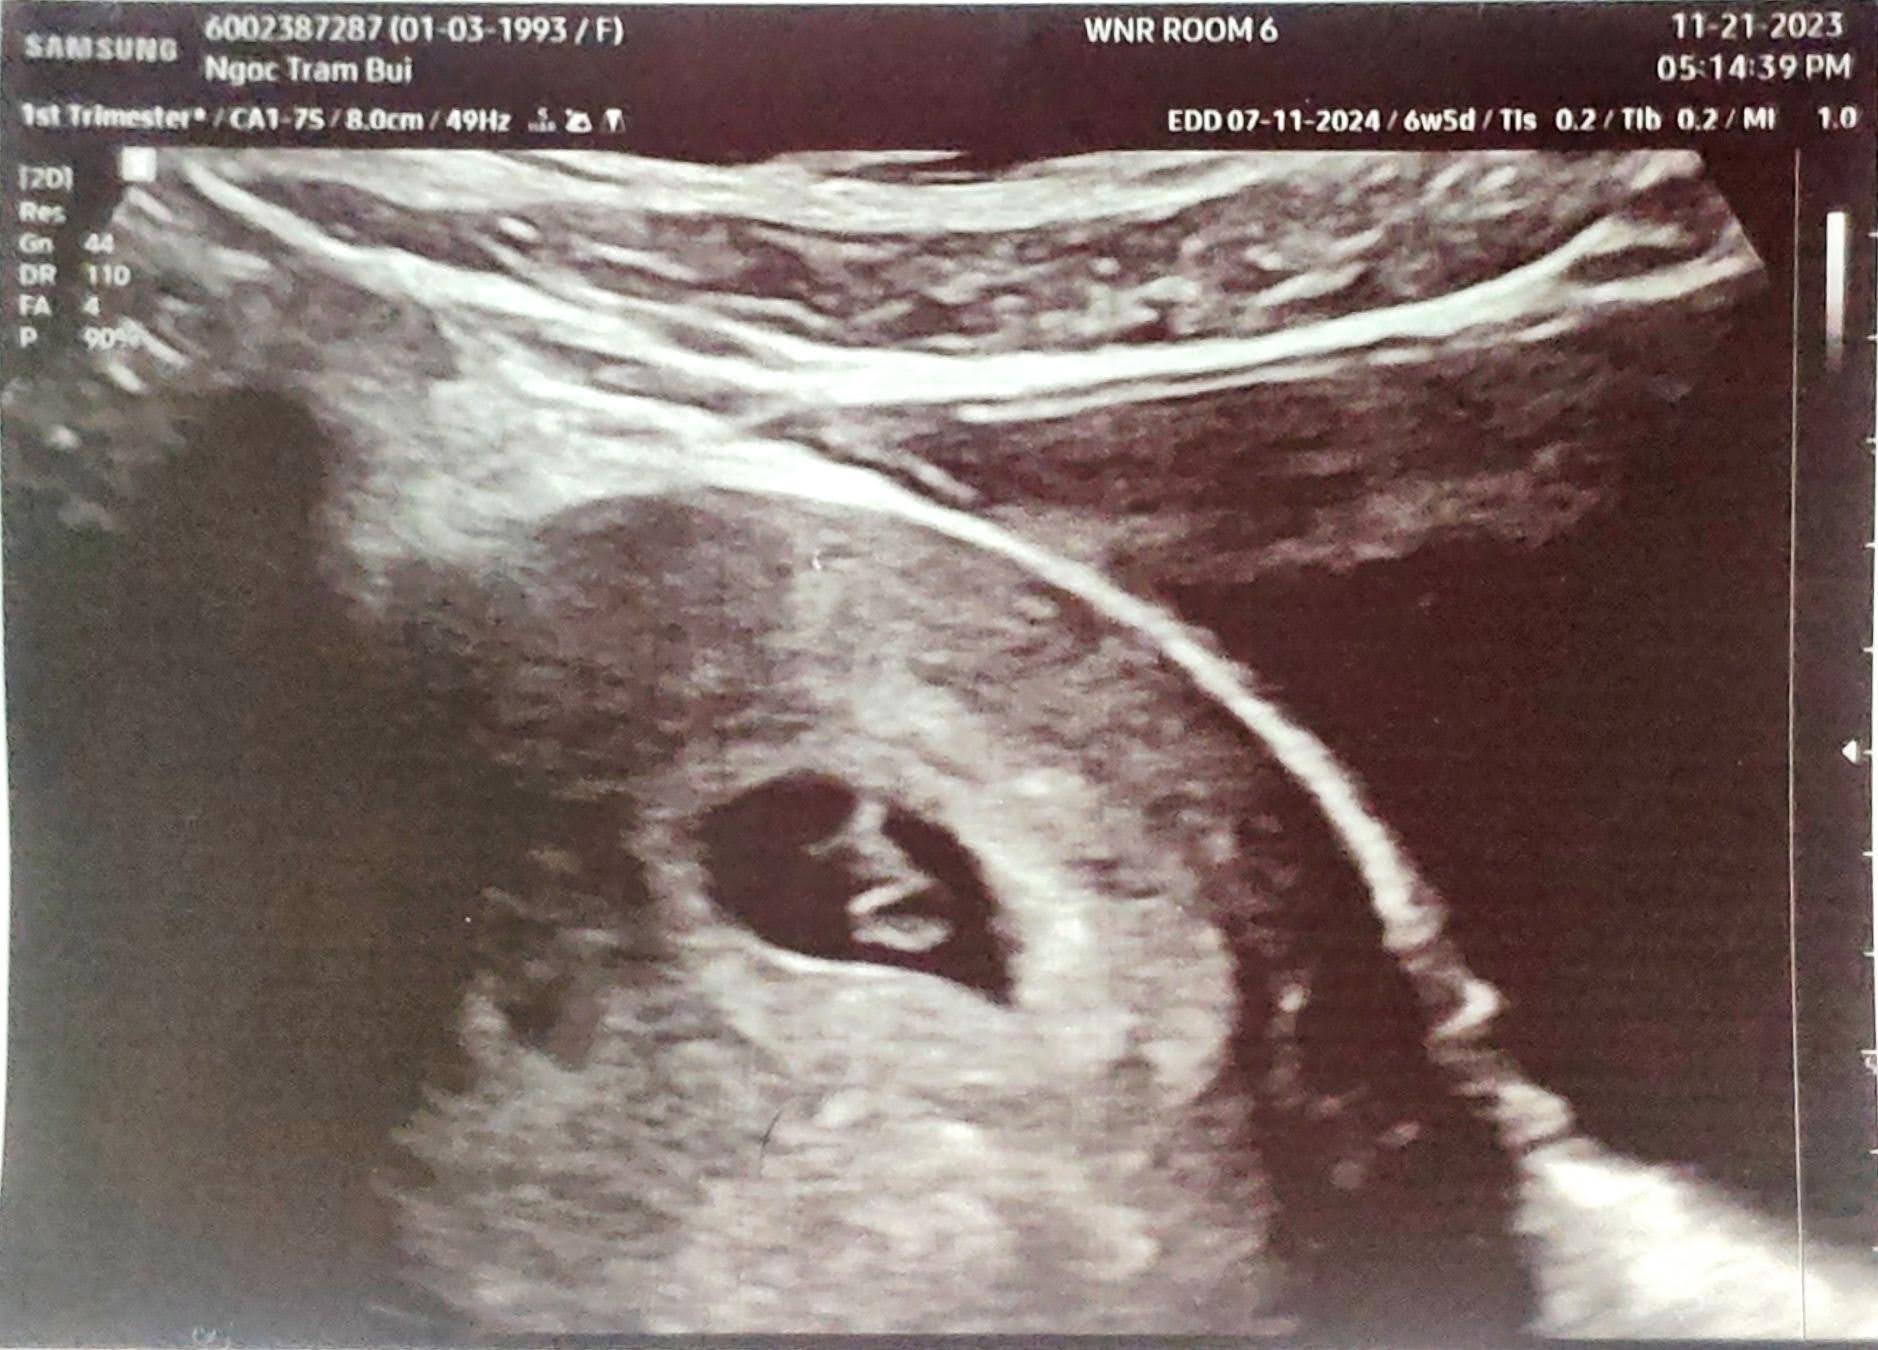

2. Đi ultrasound

7 Nov 2023

Một ngày mà hoàn tất xét nghiệm máu và siêu âm. Niềm vui khôn xiết vì đã thấy được tim thai